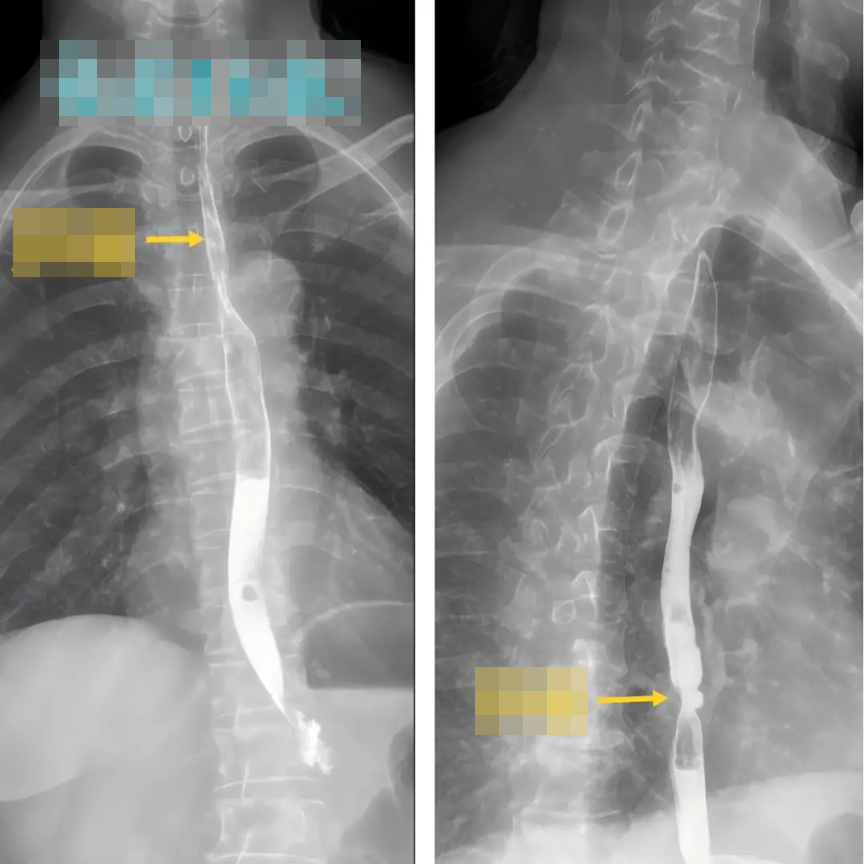

A shocking medical case has drawn attention after a couple was diagnosed with esophageal cancer during a routine health check—both suffering from the same disease despite different risk backgrounds.

In January this year, a 56-year-old man and his wife from Quanzhou (Fujian, China) went for a regular health screening. The results left them stunned: both were diagnosed with esophageal cancer. Fortunately, the disease was detected early and had not yet spread.

The husband had a family history of the disease, but his wife did not—raising concerns about what could have caused both of them to develop cancer at the same time.

After reviewing their lifestyle, doctors identified a key factor: their long-term habit of consuming very hot drinks and foods, especially hot tea, soup, and hot pot.

After diagnosis, the couple underwent minimally invasive surgery. Just five days later, they were discharged, and within about a week, they were able to gradually return to a normal diet.